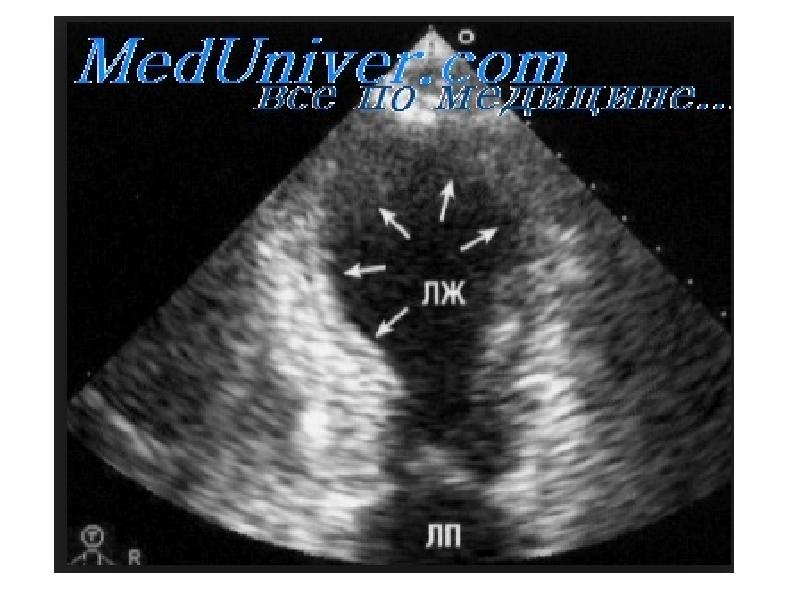

Здоровье сердца: УЗИ при рестриктивной кардиомиопатии